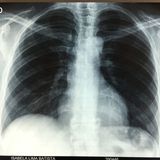

Tuberculous pneumonia

Immunocompetent patient